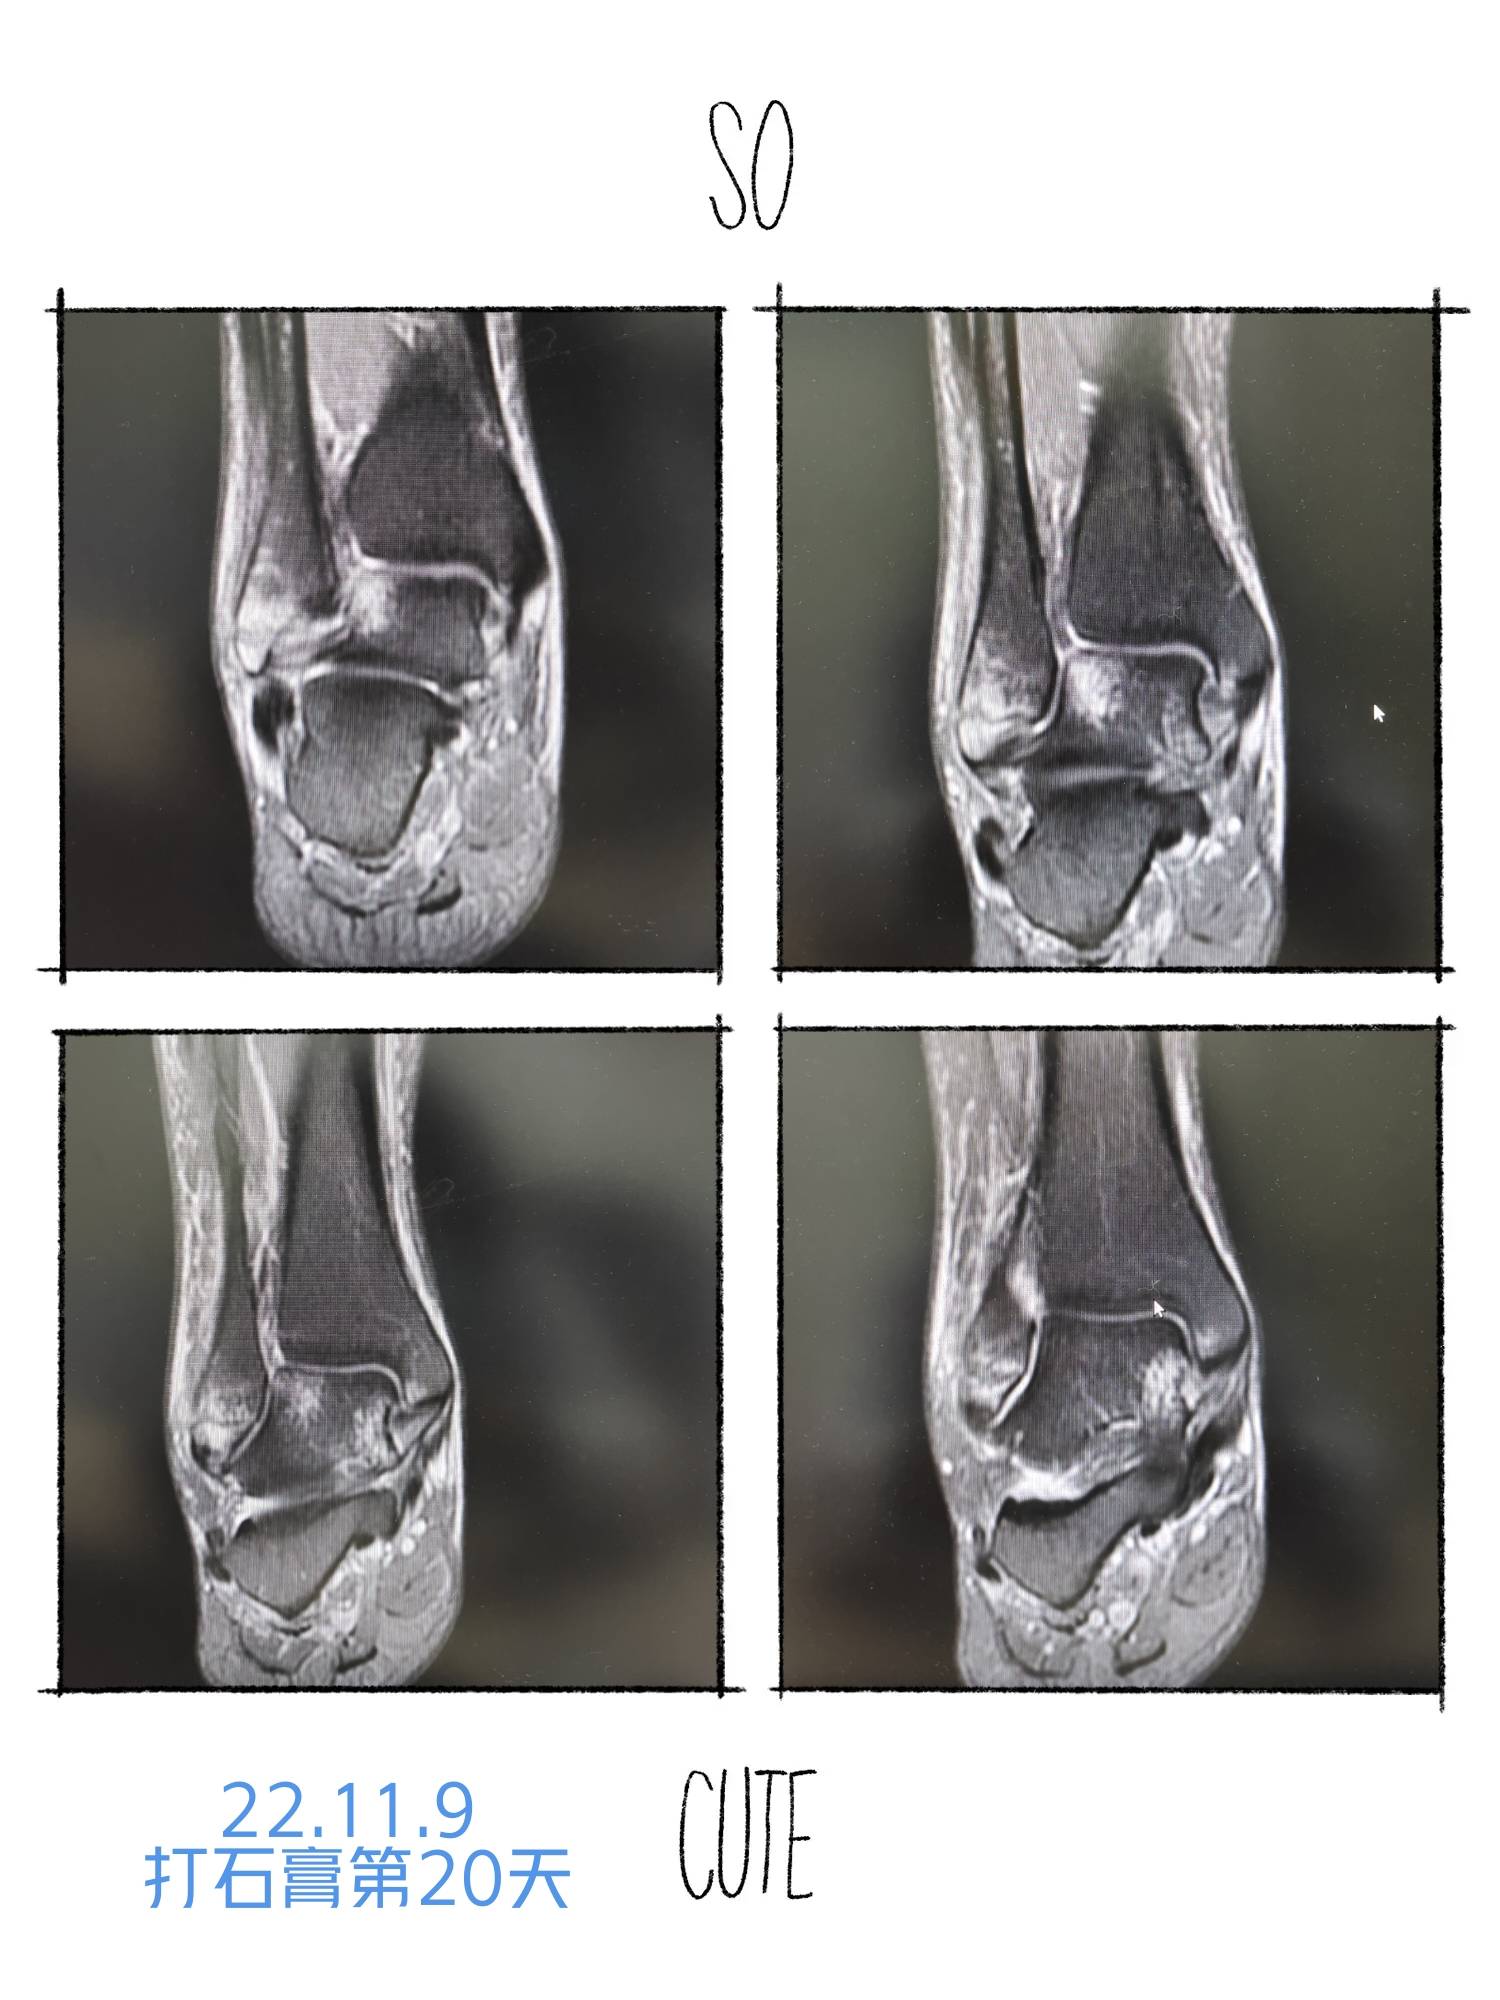

22.11.9踝关节核磁共振检查,组织水肿和挫伤。骨折位置对位很好,医生建议继续石膏固定,不能负重。